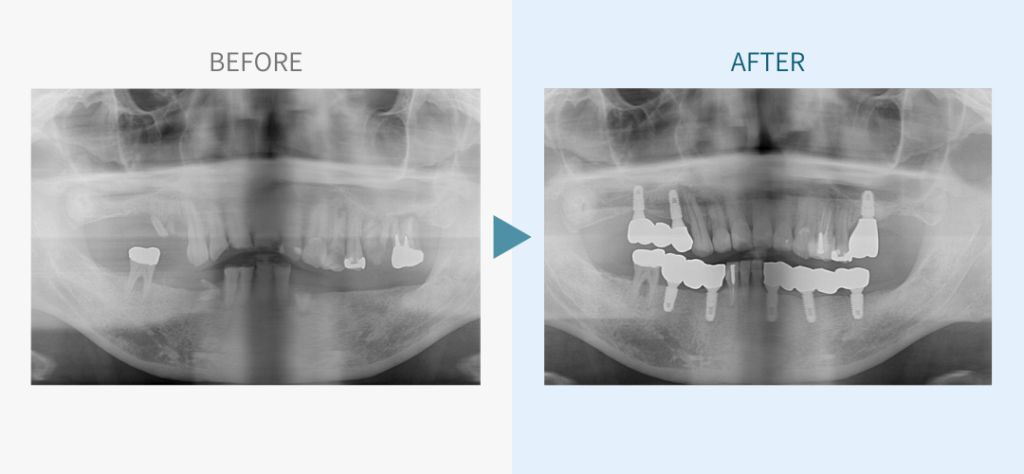

デンタルチームジャパンでは、サイナスリフト(上顎洞底挙上術)や骨造成など、他院で「骨が足りない」と断られた難症例にも対応しています。

こちらではその一部の症例についてご紹介します。